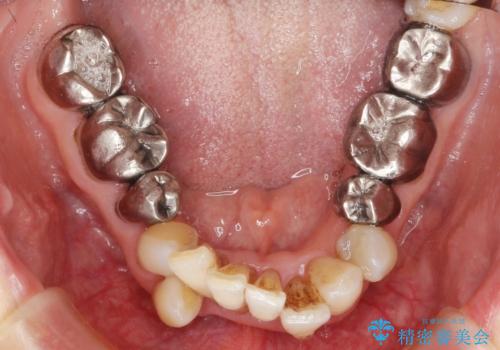

- 前歯の見た目・歯並び・銀歯の見た目の改善を求めて来院されました。

まずガタ付きの強い歯並びをマウスピース矯正インビザラインで整えたのち、セラミック治療による審美性の改善を計画します。